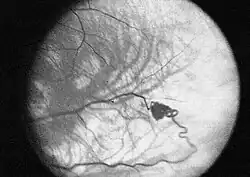

- Die retinalen Hämangiome können eine mehr angiomatöse oder mehr fibrosierende Ausprägung haben. Dies ist für die Prognose der Erkrankung in Bezug auf das Auge sehr wichtig. Bei mehr angiomatösen Hämangiomen überwiegt der Gefäßanteil der Gewebsveränderung, was häufiger zu massiven Einblutungen in das Auge mit einer plötzlichen vollständigen Erblindung führen kann. Fibrosierende Hämangiome verursachen eher eine Traktionsveränderung der Netzhaut. Wenn die Hämangiome in der Peripherie der Netzhaut gelegen sind, verursachen sie häufig keinerlei Beschwerden; liegen sie dagegen zentral, kann bald eine Visusminderung auftreten. Wenn die Gefäßknäuel direkte Verbindungen zwischen Venen und Arterien ausbilden, kann es zum Austreten von Gewebsflüssigkeit im Auge kommen mit den entsprechenden Folgen (Druckerhöhung).

Zum Verlauf der Erkrankung werden sehr unterschiedliche Angaben gemacht. Die retinalen Angiome werden im Durchschnitt bei den Patienten im Alter von 25 aufgedeckt. Die Netzhautveränderungen können, sofern sie rechtzeitig entdeckt werden, gut behandelt werden. Die intrazerebralen und spinalen Hämangioblastome können vor allem im Bereich des Hirnstammes zu gefährlichen Blutungen führen.

Die Laserkoagulation wird zurzeit bei kleineren retinalen Hämangiomen angewendet. Dabei werden Argon-,[10][11] Krypton-,[12] Farbstoff- und Diodenlaser, früher auch Xenon-Koagulator, eingesetzt. Der Vorteil des Verfahrens ist die gezielte Zerstörung mit genauer Dosierung, wobei das gesunde Gewebe geschont wird.[13] Durch häufige Anwendungen der Methode zeigen sich Erfolge bei retinalen Hämangiomen bis zu einer Größe von 4,5 mm, allerdings ist die Therapie am effektivsten bei Größen bis 1,5 mm (entspricht einem Papillendurchmesser) oder kleiner.[14][15][16] Angiome, die größer als ein Papillendurchmesser sind, zeigen bei der Laserkoagulation nur unbefriedigende Ergebnisse und sollten daher mit anderen Methoden behandelt werden.[17] Die Laserkoagulation kann direkt auf das Angiom erfolgen, auf die zuführende Gefäße des Angioms oder beides gleichzeitig.[18] Die Ansprechrate bei der direkten Photokoagulation bei der Benutzung vom Argon-Laser liegt bei 91 – 100 %.[15][19] Hämangiome mit der Größe von einem Papillendurchmesser brauchen durchschnittlich drei Anwendungen bis zur vollständigen Verödung, hingegen ist bei Mikroangiomen eine Sitzung meist ausreichend.[17] Einige Autoren empfehlen die Kombination der Laserkoagulation mit anderen Methoden, um Angiome zu behandeln, die durch die alleinige Laserkoagulation nicht ausreichend behandelt werden konnten.[20]